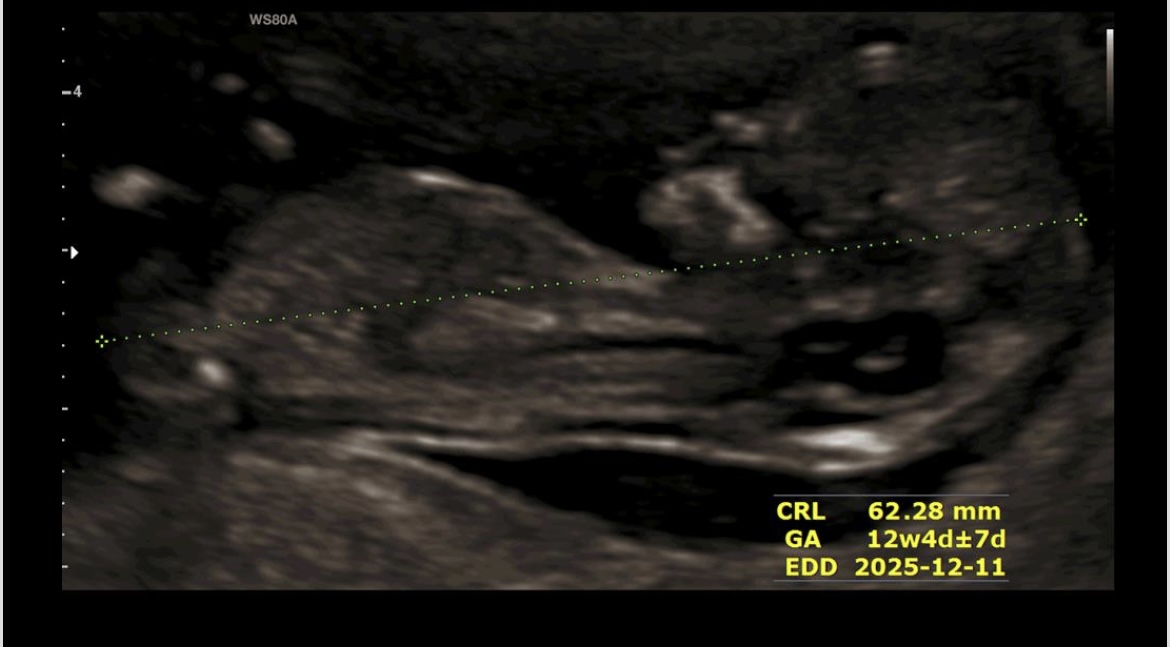

bahar1432 مدیر استارتر عضویت: 1402/01/21 تعداد پست: 75 عنوان سونو ان تی 32 بازدید | 1 پست بچها بنظرتون بچم چیه؟ 1404/03/12 | 20:11 0 نفر لایک کرده اند ... گزارش تاپیک نامناسب